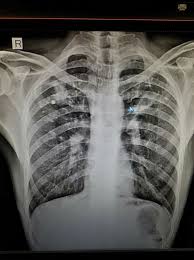

Chest X Ray To Check Fitness Is Outdated Health Gulf News

Chest X Ray To Check Fitness Is Outdated Health Gulf News from gulfnews.com